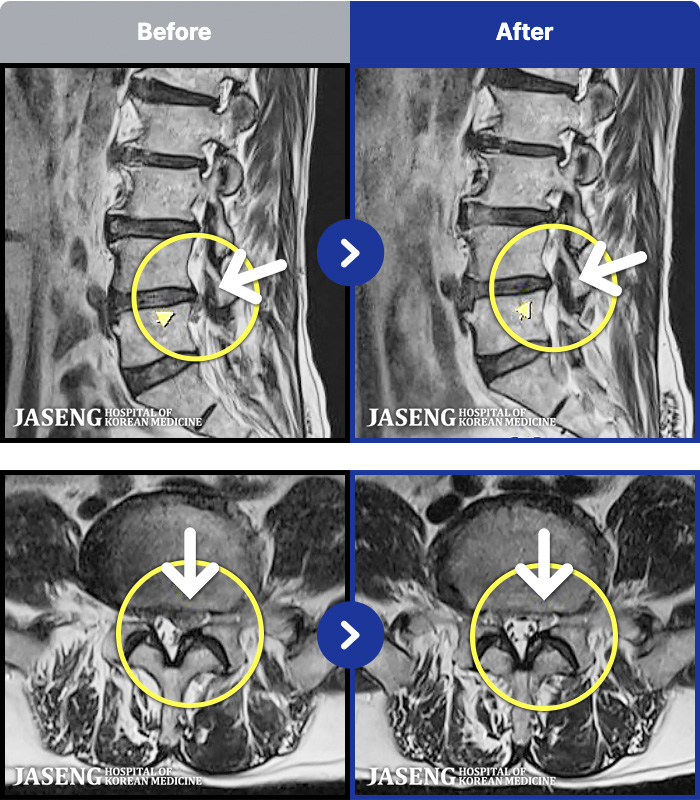

MRI ġ

1,301 MRI ũ ʸ Ȯϼ.